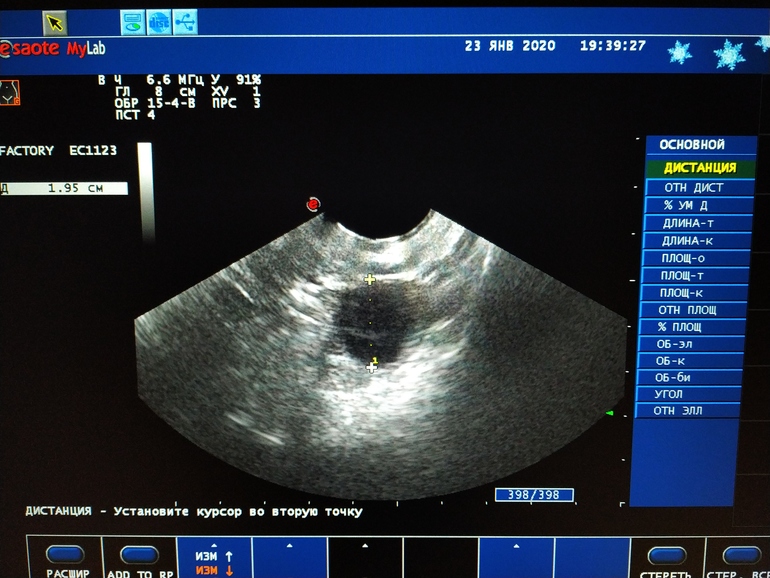

АнализыВот так вот.. поза вчера только жаловаль на свой график БТ, а вчера на узи 13дц мне Г сообщает что Ф 2см и шикарный эндометрий 9,5 как подушечка хорош)))) даже сфоткать заставила и мужу дома показать